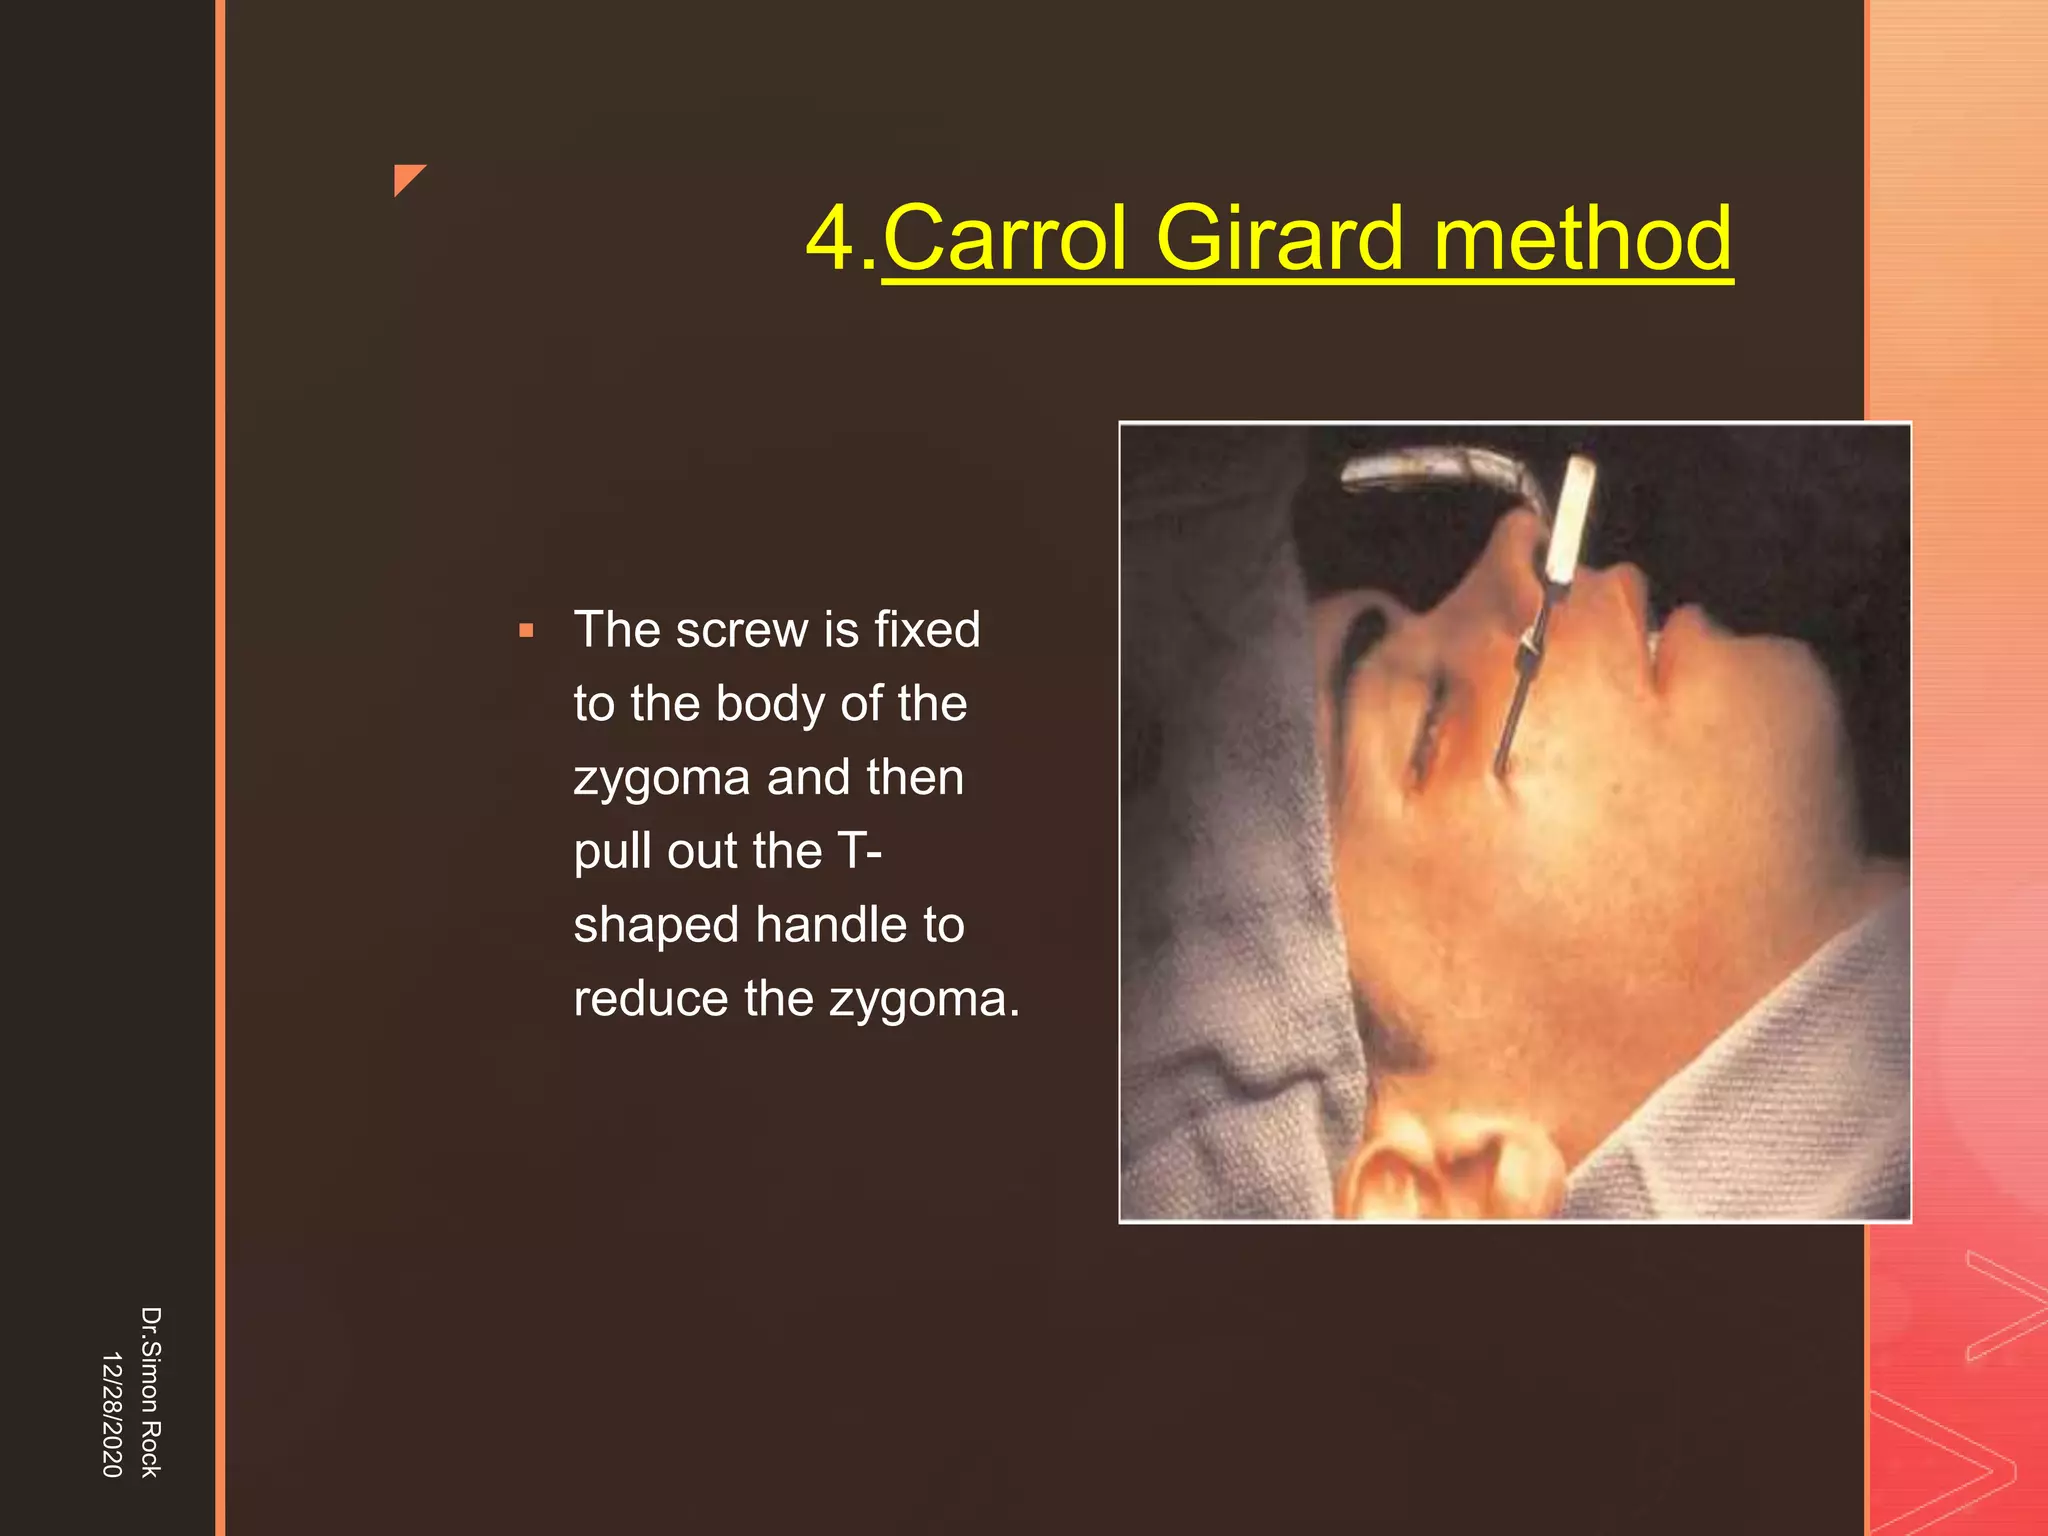

This document discusses the anatomy and fractures of the zygomatic bone. It notes that the zygoma forms the cheekbone and articulates with several other facial bones. Zygomatic fractures most commonly occur in the arch or body due to blunt trauma. Diagnosis involves checking for diplopia, ecchymosis, and other signs of orbital or facial bone involvement. Treatment may involve closed or open reduction based on the severity of displacement. Closed reduction techniques try to elevate the bone back into position without surgery, while open reduction requires surgical exposure and fixation of the fracture site.